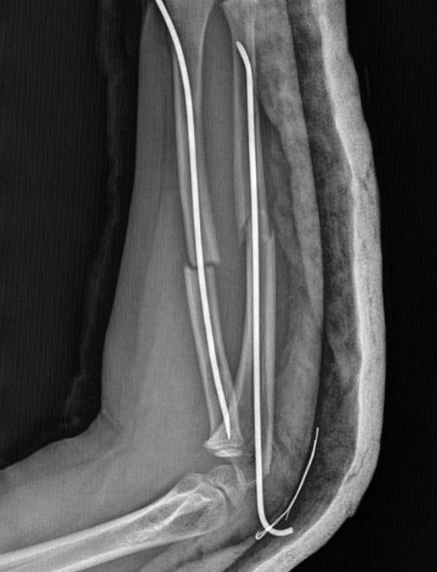

İstanbul'un Büyükçekmece ilçesi Tepecik'te bulunan bir ilkokulda, akran zorbalığının ulaştığı dehşet verici boyutlar ortaya çıktı. İddiaya göre, 9 yaşındaki bir öğrenci, 8 yaşındaki arkadaşı Y.K.Ş.'yi darp ederek kolunu iki farklı yerinden kırdı. Öğretmenler, Y.K.Ş.'nin ailesini arayarak olayı "kavga etti, kolunu duvara çarptı" şeklinde bildirirken, hastanede yapılan incelemede çocuğun kolunun iki ayrı yerden kırıldığı ve acilen ameliyata alınarak platin takıldığı öğrenildi.

Olay, geçtiğimiz ay Büyükçekmece Tepecik'te bulunan bir ilkokulda meydana geldi. İddiaya göre 8 yaşındaki Y.K.Ş. okulda bir süredir kendisini rahatsız eden 9 yaşındaki çocuk tarafından darp edilerek kolu ikiye katlandı. Y.K.Ş.'nin 2'ye katlanan kolu 2 ayrı yerinden kırıldı. Öğretmenler Y.K.Ş.'nin ailesini arayarak, ‘oğlunuz arkadaşıyla kavga etti duvara çarptı' denildi. Oğlunu okuldan alıp hastaneye götüren anne Songül Gökdemir, oğlunun kolunun 2 ayrı yerinden kırıldığını öğrenip ameliyata alınacağını duyduğunda büyük şok yaşadı. Konuyla ilgili anne Gökdemir savcılığa giderek şikayetçi oldu. Savcılıktan ise 'söz konusu Suça Sürüklenen Çocuğun yaşının 12'den küçük olduğu gerekçesi ile kovuşturmaya yer yoktur' kararı çıktı. Anne Gökdemir karara itiraz ederken mağdur Y.K.Ş. ise haftalardır okula gidemiyor. Eğitimi aksayan çocuğun 2 hafta sonra ise platinlerinin çıkarılması için yeniden ameliyata gireceği öğrenildi.

Yaşanan olayı anlatan Songül Gökdemir, " Arkadaşlarından darbe aldığını biliyordum. Ayrıca Eylül ayından bu yana bir arkadaşının onun kolunu kırmaya çalıştığını söyledi. Ben de 'arkadaşını öğretmene söyle' dedim. Bundan kaçıyordu. O gün de rehber öğretmenine bu arkadaşını şikayet ettiler. Ben işe gittim 1 saat sonra öğretmeni aradı. Oğlunuz arkadaşıyla birbirini itekledi kolunu duvara çarptı gelir misiniz ?' dedi. Kendi imkanımla hastaneye götürdüm. Okula gittiğimde de oğlum derste oturuyordu. Öğretmen ders işliyordu ambulans çağırılmamış. Hastanede kolunda 2 tane kırık olduğunu acilen de ameliyata girmesi gerektiğini öğrendim. 3 gün sonra ameliyata alındı. Kolundaki platinlerden dolayı her gün pansumanı var. 2 hafta sonra tekrar ameliyatı var" dedi.